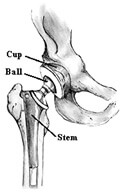

In osteonecrosis, it often comes down to a decision for replacement of the damaged tissue of the hip. The artificial components of the hip come in two basic types; the acetabular component (or hip socket portion) is designed to replace the natural acetabulum, while the femoral component (or hip stem portion) will replace the pivoting femoral head. Diseased bone may be replaced with a wide variety of materials, including other pieces of bone, shaped metal, polyethylene, or even ceramic held in place either with or without forms of cement.

A completely artificial replacement of the damaged joint, known as a joint prosthesis, is classified as a Total Hip Arthroplasty or simply Total Hip. This means that the articular surfaces of the acetabulum and the femur are replaced.

When only the femoral head is replaced and no alteration is made to the natural acetabulum, the procedure and resulting prosthesis is referred to as a half, or Hemiarthroplasty.